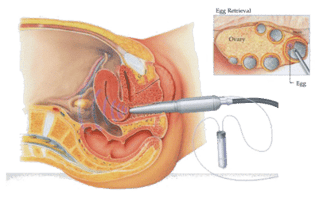

The egg retrieval procedure

When your or your partner's leading follicles reach 18 - 20 mm (average diameter) in size and estradiol hormone (E2) level increases, your eggs are ready for harvest.

36 hours after the hCG injection course, your doctor will schedule the egg retrieval procedure. For example, if you self-administer the injections on a Monday at 9:00 PM, the egg retrieval procedure will occur on Wednesday at 9:00 AM. Here's a comprehensive overview of the egg retrieval process:

Your doctor will guide a needle attached to an ultrasound probe through the guide. Each follicle is then punctured, and the fluid (along with the egg floating in it) is aspirated. Once the liquid is sent to the laboratory, the embryologist searches for, isolates and treats the eggs for freezing or fertilization.